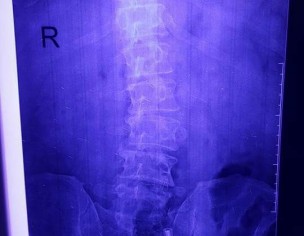

X-ray's shows it's structural or postural, need examination.